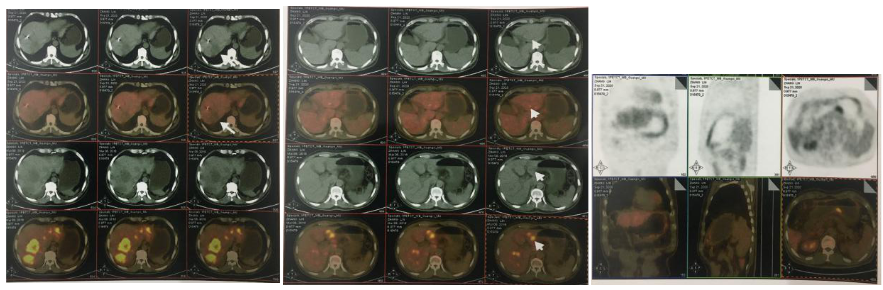

2018-03-08 PET/CT示:胃癌(?)并全身多发淋巴结转移、肝脏多发转移、双肺上叶多发转移;

△2018-3-19基线CT

2018-11-14 CT(8周期化疗后):PD?

△基线水平

△治疗后

2018-11-19 PET/CT

胃壁代谢稍增高但未见明确的肿物,肝内低代谢结节考虑转移瘤治疗后活性减低,纵膈及右肺门两个淋巴结代谢增高,考虑转移瘤活性尚存、左侧颞骨局部骨质破坏并代谢增高,考虑转移瘤。